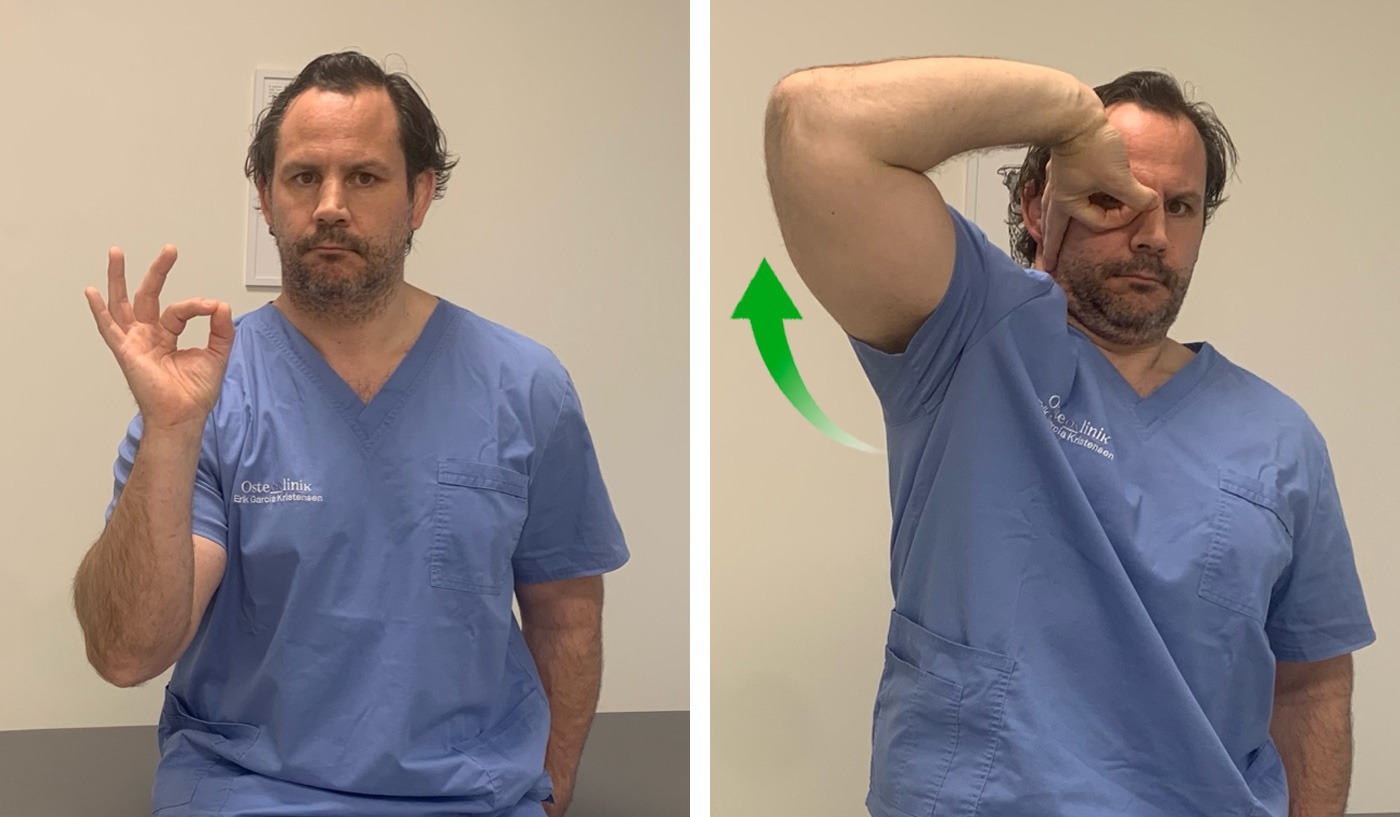

3. Nervio Cubital

Vamos a realizar, primero, una puesta en tensión y estiramiento del nervio para después pasar a una movilización.

Partimos de una posición erguida de pie o sentado.

Con el pulgar y el índice hacemos “pinza” describiendo un pequeño círculo.

Vamos a realizar una flexión del hombro elevando el codo, a la vez que hacemos flexión del codo y flexión dorsal de la muñeca como si quisiéramos colocarnos unos “anteojos”.

Muy probablemente no consigamos llegar hasta colocar la palma de la mano en nuestra cara. No importa, llegamos lo más cerca que podamos.

De esta manera estamos poniendo en tensión el nervio cubital y podemos sentir la sensación de tensión y cierto hormigueo en el brazo y la mano.

Para movilizar el nervio, vamos a repetir esta secuencia bajando el codo y estirándolo y haciendo flexión palmar de la muñeca. Y volviendo de nuevo a la posición de estiramiento.